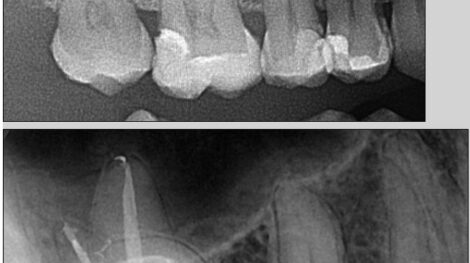

Leczenie kanałowe pierwszego przedtrzonowca z 3 kanałami